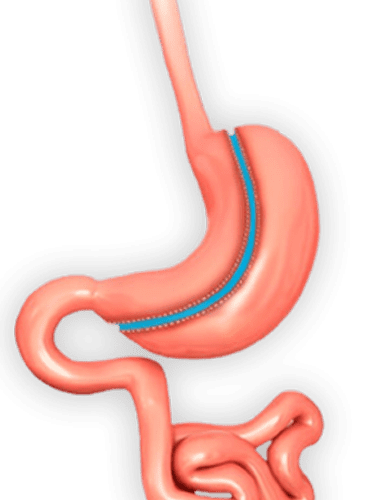

Операция ръкавна гастректомия- метод на извършване, възстановителен период и предимства

Въпреки, че затлъстяването се възприема като естетичен проблем в много отношения то е изключително важен здравен проблем, който се нарежда на началните места сред предотвратимите заболявания, които причиняват смърт в световен мащаб. Причините за затлъстяване са много и могат да включват генетични фактори, липса на физическа активност, неправилно хранене, психологически проблеми и много други. Болестното...